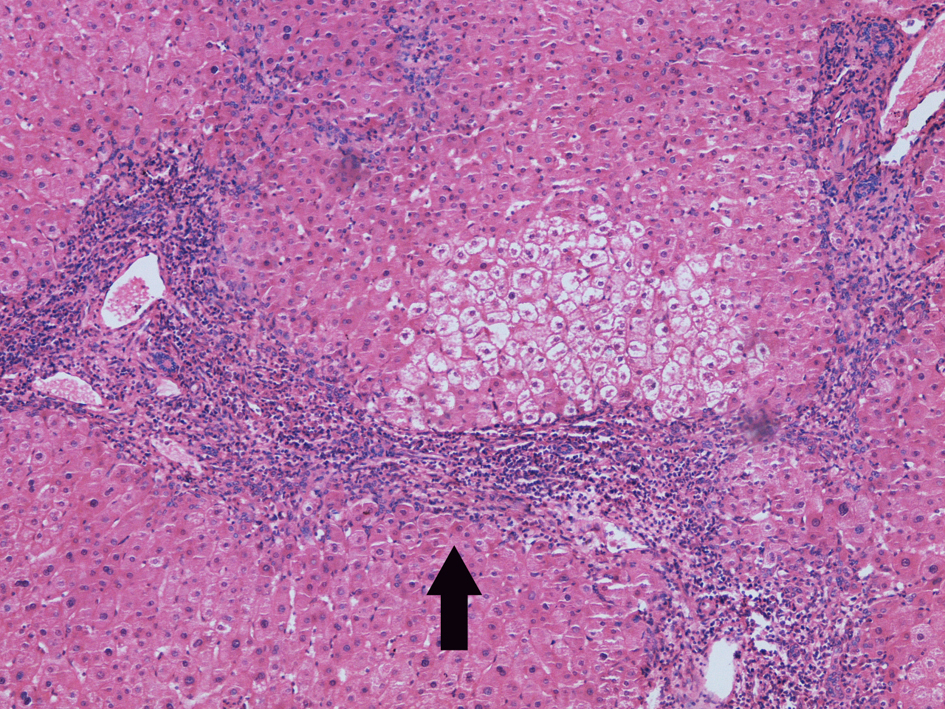

3.慢性活动性肝炎